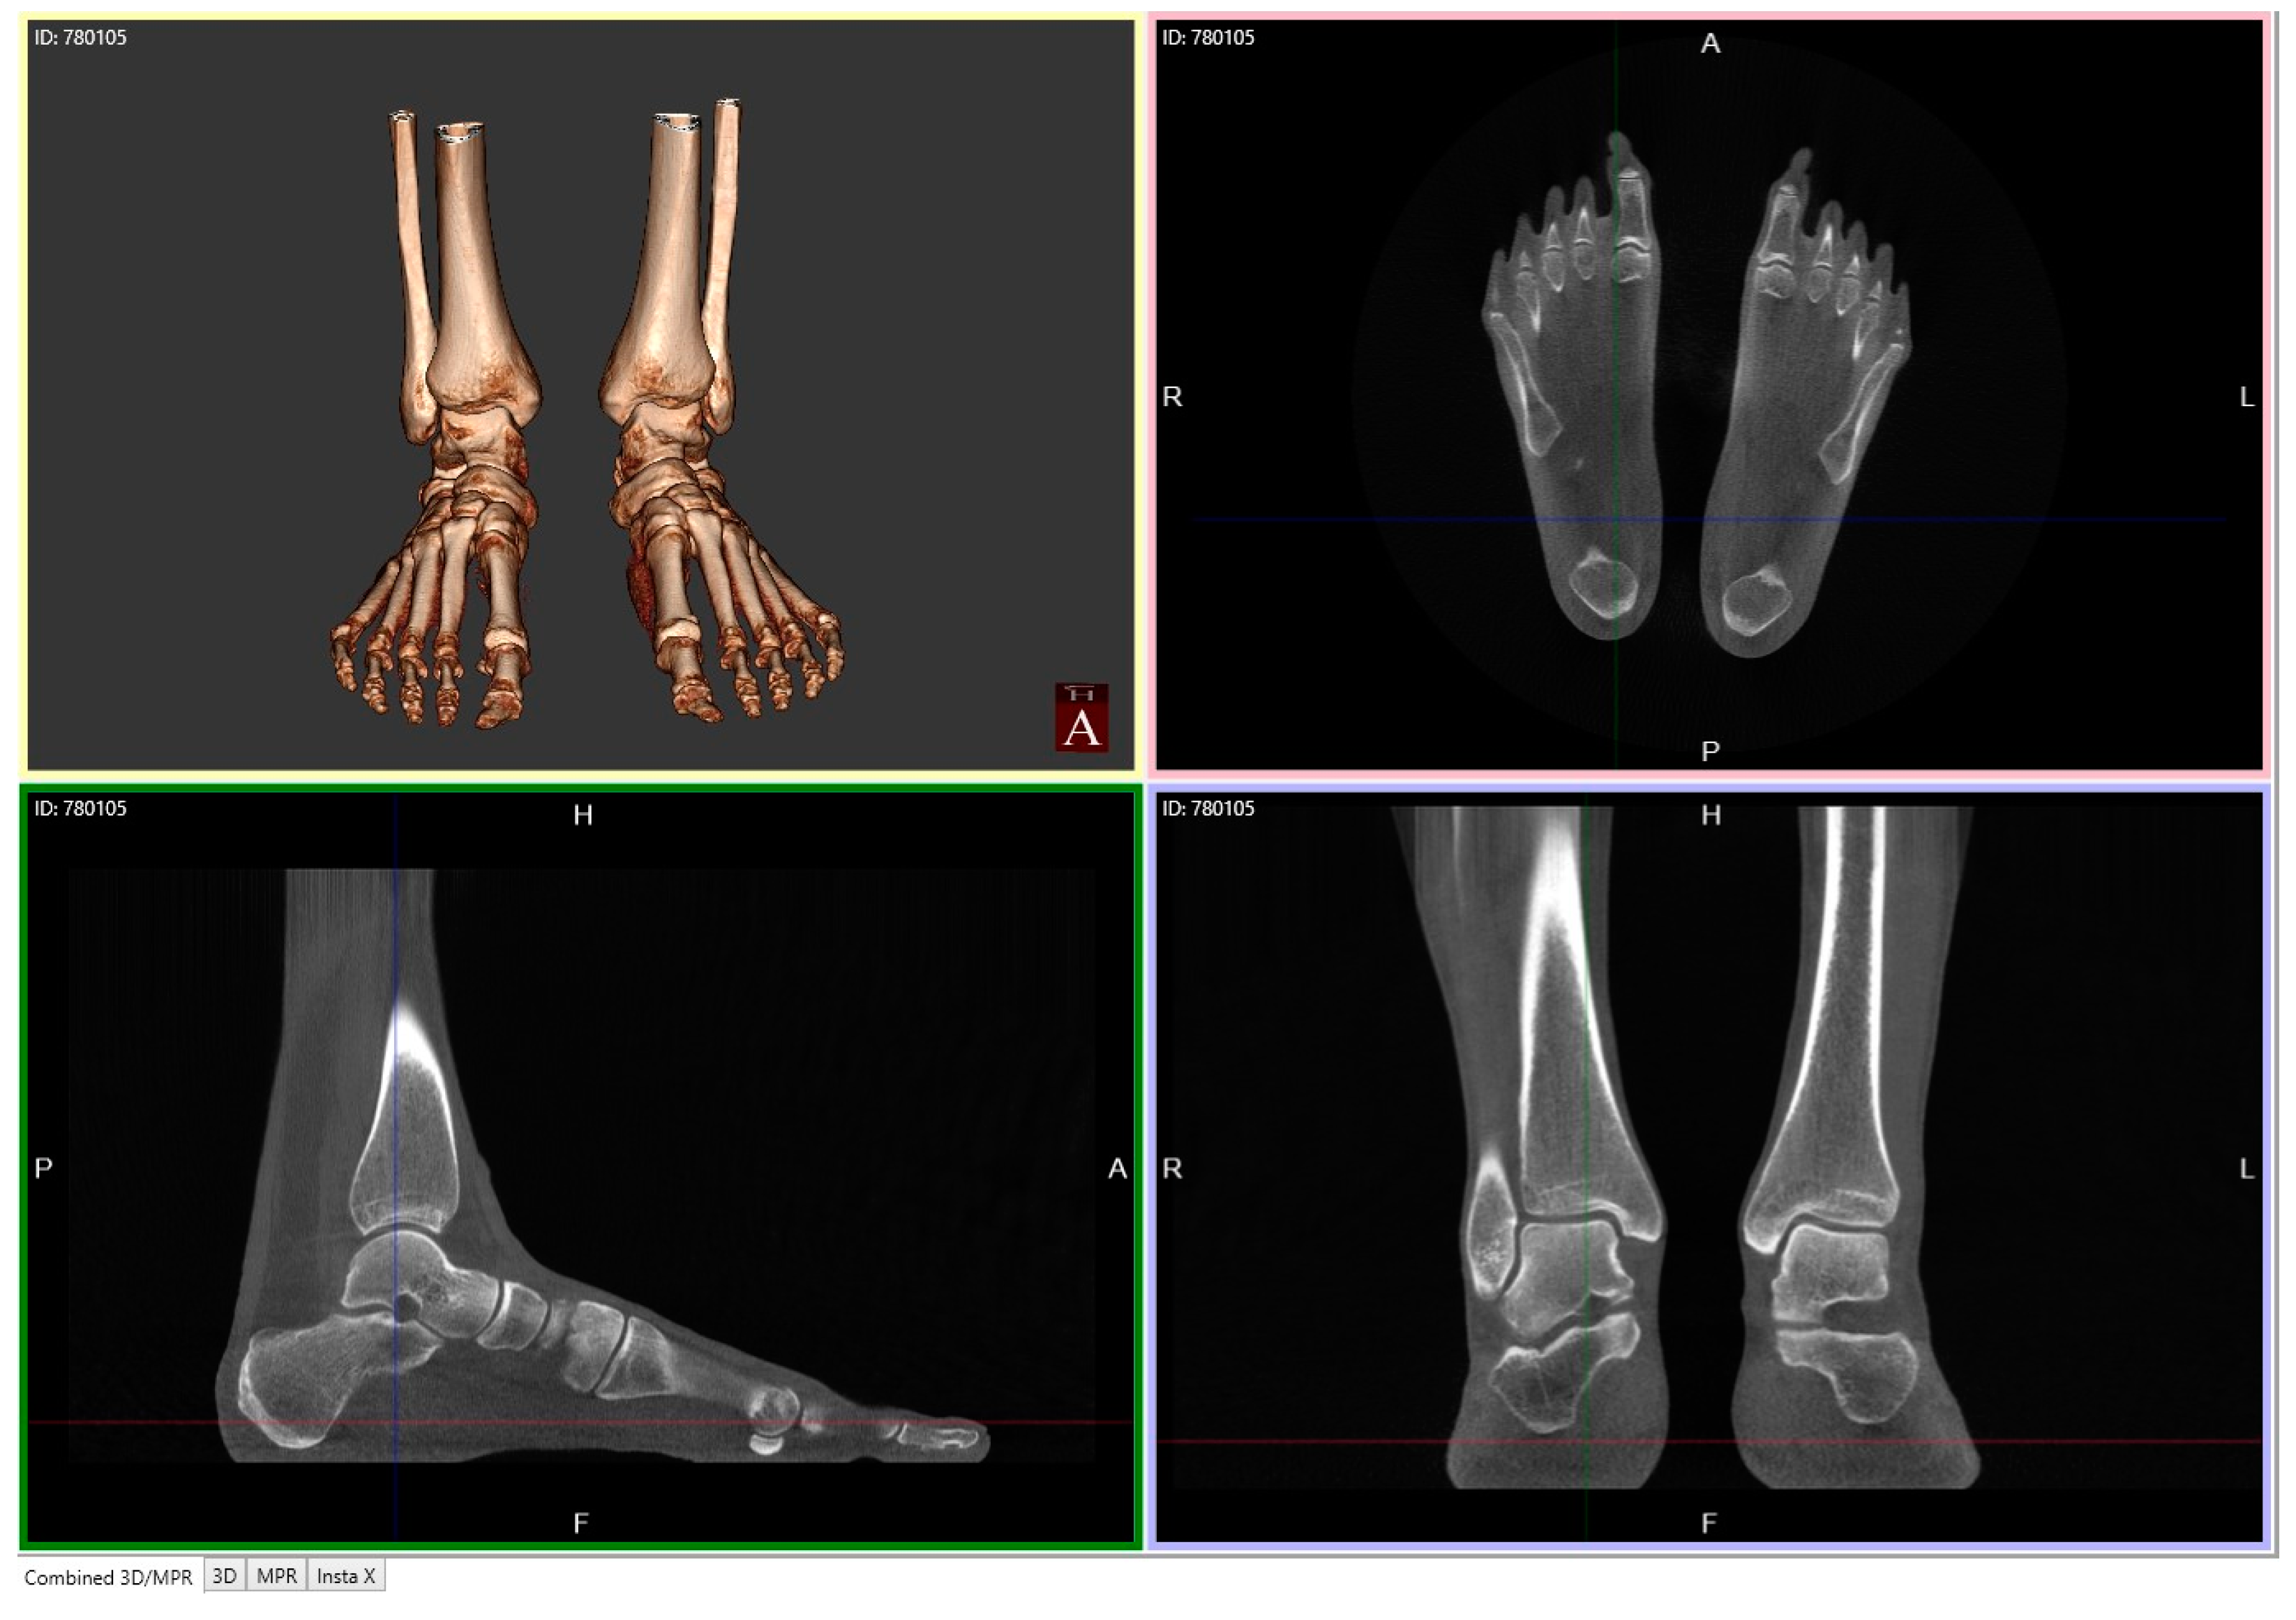

4.2.1. Description of Techniques for Image Acquisition

4.2.2. Description of Advanced Computerized Techniques for Image Processing